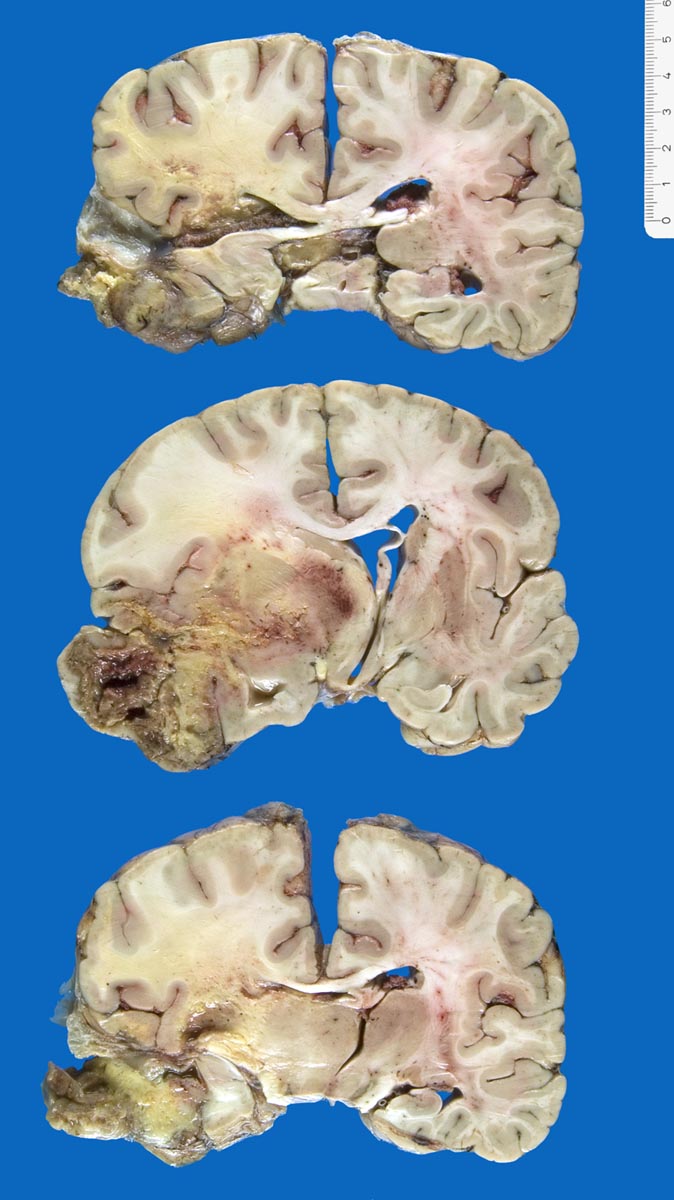

Lokalisation:

Bevorzugte Lokalisationen sind das Marklager des Frontal- und Temporallappens. Glioblastome des Hirnstammes sind selten und betreffen meist Kinder. Von dort breiten sie sich oft über den Balken schmetterlingsförmig auf die Gegenseite aus. Weniger als 5% der Tumoren wachsen multizentrisch. Eine Aussaat in den Subarachnoidalraum mit Metastasierung über den Liquor findet sich selten. Noch rarer sind hämatogene Metastasen in extraneurale Organe.

Morphologie:

Die Schnittfläche ist auffallend bunt. Dies ist bedingt durch ein Nebeneinander von graurotem vitalem Tumorgewebe, gelben Nekrosen, roten Einblutungen und gelegentlich grünlichen Gallertzysten.